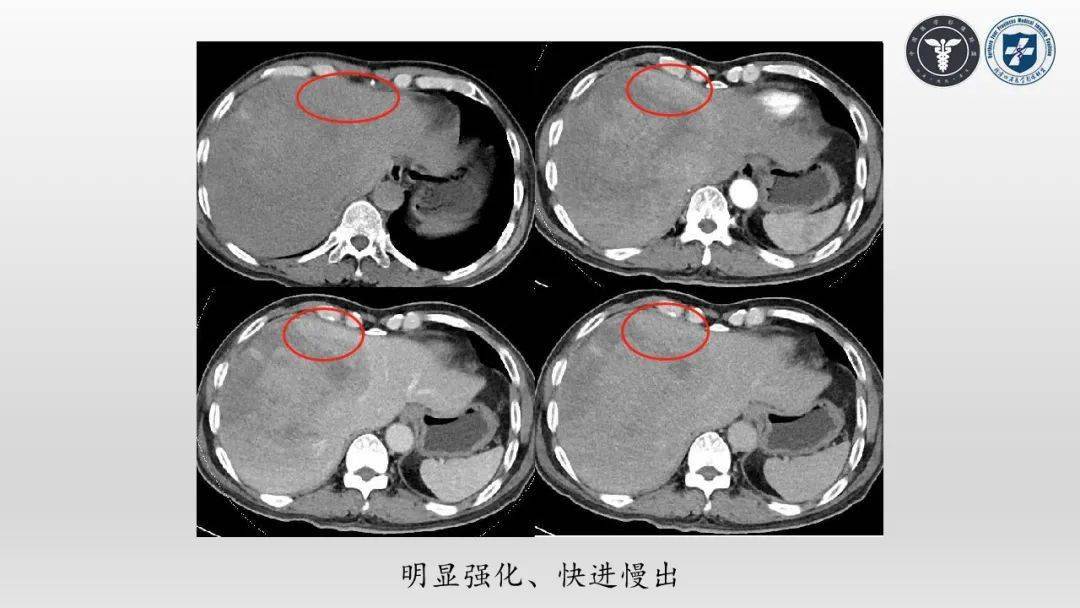

视频丨陈春茂肝脏转移性黑色素瘤病例分析